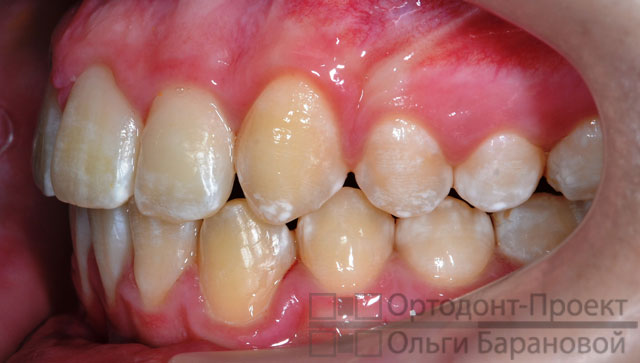

Диагноз ортодонта: глубокий дистальный прикус, сужение и удлинение верхнего зубного ряда, сужение нижнего зубного ряда.

Несмотря на сильное выступание передних зубов брекеты незаметны.

Через 7 месяцев зубы стали значительно ровнее: